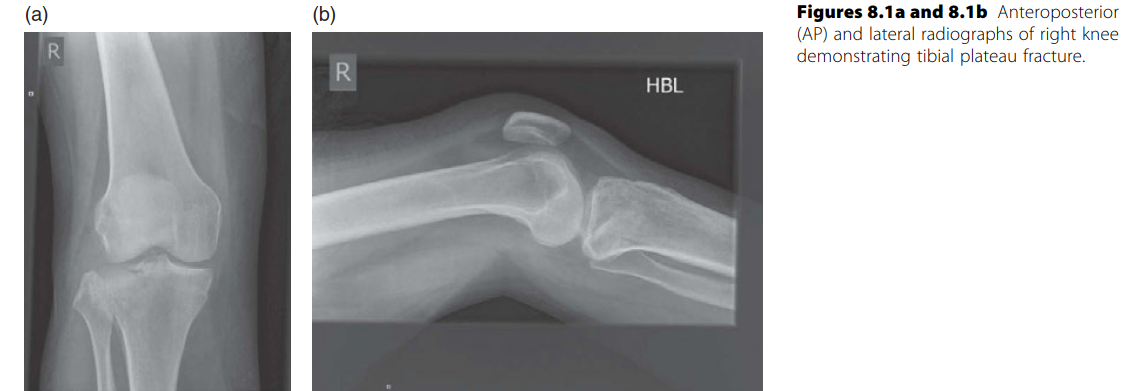

Lower limb Trauma Structured oral examination question 6 A 50-year-old woman, front-seat passenger, was invol…